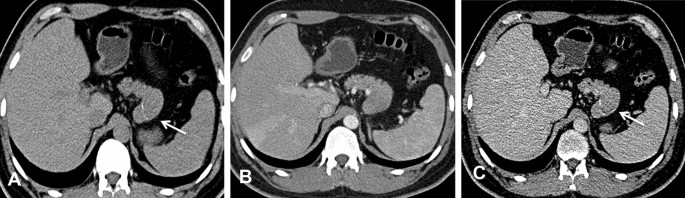

CT images of a 36-year-old man with surgically confirmed PB. (A) Nonenhanced CT scan revealed an exogenous mass with calcification in the tail of the pancreas (arrow). (B) The tumor exhibits an exophytic growth pattern, similar to branches growing outward from a tree trunk. In the AP, the tumor showed uniform enhancement, but the degree of enhancement was lower than that of the normal pancreatic parenchyma. (C) In the VP, the tumor presented as a well-defined mass with enhanced encapsulation (arrow) that had slightly less enhancement than the normal pancreatic parenchyma.

A total of six tumors (85.7%) were completely solid (Figs. 1, 2, 3, 4) with an average diameter of 5.28 cm, and one tumor showed mixed solid and cystic characteristics. No significant central necrosis was found. Calcification (Fig. 2A) was observed in one mass (14.3%). One patient exhibited hemorrhage, which presented as a high-density region on nonenhanced CT scans. Three tumors (42.9%) had thin, well-circumscribed, enhanced encapsulation (Fig. 2C). One patient exhibited a pancreatic head tumor with mild dilatation of the pancreatic common duct, and no patients suffered from pancreatic atrophy. Two tumors showed isointensity on T1-weighted imaging (T1WI) (Fig. 1A), while on T2-weighted imaging (T2WI), one tumor showed isointensity (Fig. 3B), and one showed hypointensity (Fig. 1C).

Compared with the adjacent normal pancreatic parenchyma on the noncontrast CT scan, six tumors (85.7%) showed isodensity (Fig. 2A), while one (14.3%) showed hypodensity. All tumors showed hypodensity in the AP (Fig. 3A). Four tumors (57.1%) showed hypodensity (Fig. 1D), while the other three (42.9%) showed isodensity in the VP (Figs. 2C, 4A). Six small tumors (85.7%), with an average diameter of 5.28 cm, showed homogeneous enhancement (Fig. 1D), while the large lesions showed nonhomogeneous and septal enhancement due to cystic necrosis; none of the tumors displayed ring enhancement. With dynamic contrast-enhanced MRI, all tumors (n = 2) showed hypointensity in the AP and portal phase (Fig. 1C), isointensity in the VP (Fig. 3C) as well as progressive enhancement.